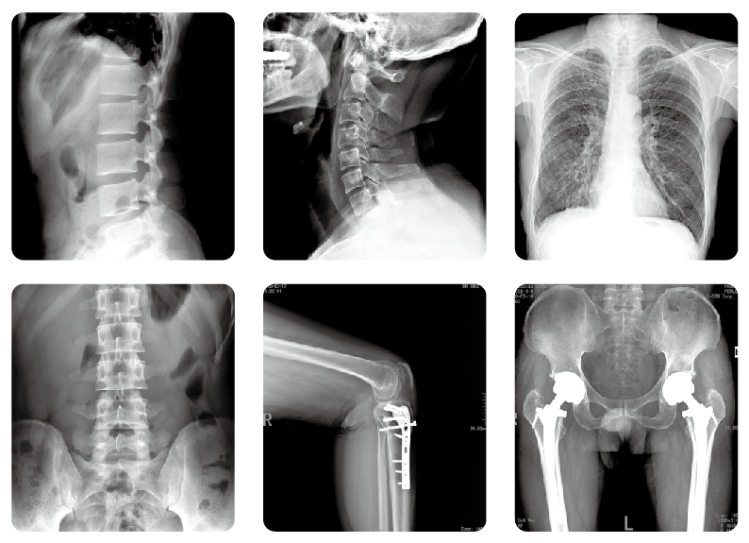

在門診,經(jīng)常會有拍片子的患者咨詢:大夫,放射科是不是到處都是射線,對我身體很不好啊?每次聽到諸如此類的問話,醫(yī)生都會有些哭笑不得,醫(yī)院放射科什么時候變得這么“恐怖”了?那么,放射科的走廊和候診區(qū)這些位置到底有沒有射線呢?會不會對人身體造成損害呢?

放射科拍片

其實,放射科的墻壁、門窗以及天花板都是特別訂制的。放射科的墻壁是加厚的,且涂抹上摻有硫酸鋇的材料,能屏蔽和消減輻射,門窗上也都鑲有鉛板,所以,除工作室內(nèi)有少量軟射線之外,過道以及走廊、等候區(qū)等位置是沒有射線的,因此,大可不必過度擔心。那我們平時拍一張普通X線檢查的輻射有多大呢?

拍攝一張普通X光胸片,其曝光率約為0.045mSv/S。拍攝一張胸部肋骨大約需要0.5S,因此接受一次胸部X線檢查,患者需要承受0.023mSv的輻射量。根據(jù)國際放射委員會制定的標準,輻射總危險度為0.0165/Sv,也就是說,身體每接受一西弗特(1Sv=1000mSv)的輻射劑量,就會增加0.0165的致癌率,以此推算,一張胸片會增加約為千萬分之零點六的危險。對其他醫(yī)學檢查來說,四肢約為0.01mSv,腹部為0.154mSv,骨盆為0.66mSv,腰椎為1.4mSv,上消化道為2.55mSv。因此單次醫(yī)學檢查導致健康人群患癌的風險在千萬分之一到十萬分之一之間。

放射科DR設(shè)備

況且,現(xiàn)在各大醫(yī)院均已全面采用DR設(shè)備,輻射劑量較普通X線照片大幅減少,常規(guī)放射檢查的劑量更在安全范圍內(nèi)。所以,除特殊個體(如懷孕早期)外,我們普通人一般不需要考慮輻射損傷的問題,完全可以安心就診。